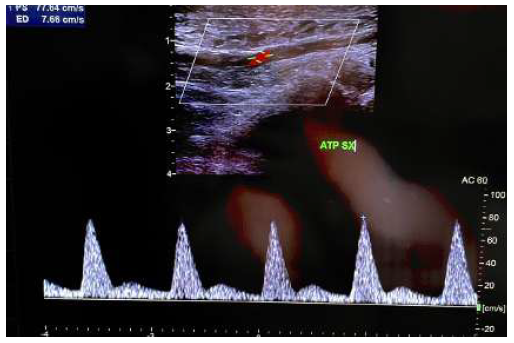

During the intervention, the patient experienced three cardiac arrests, and 15 bags of red blood cells were transfused. Immediately after the operation, the foot was warm, assuming normal colouration and pulsation at the ankle was detected. The presence of compartment syndrome was excluded. A duplex ultrasound performed shortly after the procedure showed direct blood flow to the tibial arteries, Figures 3 and 4.

Figure 3 Post operative duplex ultrasound (1). Direct flow can be observed a the level of the distal posterior tibial artery.